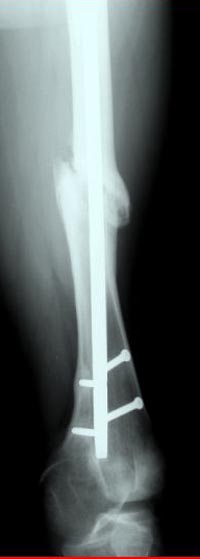

Коллеги, Комментарии к случаю лечения ложного сустава бедра аппаратом типа Илизарова, показанному здесь

Почему не замена гвоздя с рассверливанием, а аппарат?

Из истории болезни: два года назад проперирован по поводу 3А открытого перелома бедра, травма на работе в результате "стена упала на него". Сопутствующая травма: Закрытая травма черепа, перелом голеностопного сустава (прооперериван) и перелом плеча (консервативное лечение)

Лечение бедра - ургентное оперативное лечение антеградным с минимально рассверливанием, фиксацией с минимальным диаметром штифта и плюс irrigation and debridment и с закрытием поперечной до 10 см раны на уровне перелома в день поступления.

После трех дней начались выделения из ран которые промывалась в палате и рана постепенно закрылась в течение нескольких месяцев. Эмпирически получал 6 недельний курс антибиотика Vancomycin внутривенно.

Снимки представлены: 1 мес; 3 мес; 1 год; 2 года, предоперационные и ротационная КТ грамма

Деформация:

Вальгус- 17 градусов

Рекурватум 5 градусов

Укорочение 2.5см

Ротационно 22 градусов внутренная

Смещение диафиза по поперечнику 75%

Из трех вариантов:

Рассверливание с заменой более большого диаметра штифтом,

Остеотомия с фиксацией пластиной+костная пластика,

Аппарат Илизарова= Taylor spatial frame

Гвоздь для ротационных смещениц был бы идеальным имплантом, после коррекции есть возможность блокировать, но из-за укорочения метод оставил на последнее место. Есть метод Сhaplan лечения ложных суставов бедра, где необходимость bone graft, накладывается феморальный дистрактор и после удаления штифта - рассверливание, через проксимальный канал вводят костный графт в место ложного сустава под рентген контролем, потом вводят штифт, кстати, само рассверливание дейстивует как стимулятор - активизирует восстановительный процесс.

Обычный мой первый выбор - вариант с пластиной, - учитывая бывшую инфекцию, открытую травму, посчитал метод менее приемливым.

Еще больной был противв костной аутопластики, да и самому тоже хотелось перейти к истокам "откуда мы" более усовершенствованному Курганскому методу.

Операцию провели в два этапа, сперва удалили штифт, рассверливание римером на пару мм большего диаметра, определение чувствительности на анаэробную и аэробную культуру (где исследования показали негативный результат чувствительности), через дней десять - начали аппаратную фиксацию.